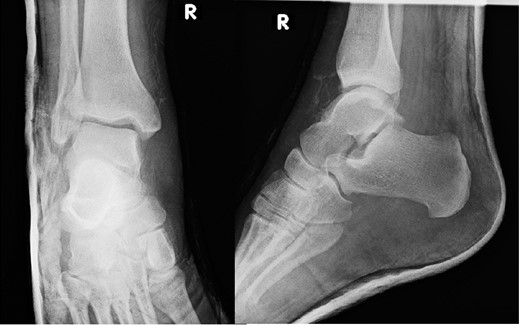

A 30-year-old male patient presented to Emergency Department (ED) following a run over injury. The patient described the mechanism of injury as moving his body over his run over foot. On clinical examination, there was obvious deformity and swelling of the right ankle. Dorsalis pedis pulse was felt but weak compared to the contralateral side with a capillary refill time under 3 s. The posterior tibial artery could not be palpated because of the deformity. X-rays showed posterior ankle dislocation without associated fractures (Fig. 1). Urgent reduction of the dislocation was done under sedation in ED. The knee was first flexed to relax the tendon Achilles then longitudinal traction with gentle forward force applied to the heel with immediate reduction of the deformity achieved. The foot was reassessed for vascular status. Triphasic pulse in both drosalis pedis and posterior tibial artery was detected with hand held Doppler. Ankle was immobilized in posterior below knee back slab to accommodate for swelling and check x-rays confirmed reduction of the ankle joint (Fig. 2). CT scan was done afterwards to define any subtle incongruity or osteochondral fragments entrapped in the joint. CT did not show any associated fractures and showed congruent reduction of the ankle joint (Fig. 3). Patient was mobilized touch weight bearing for first 2 weeks. The back slab was changed for weight bearing short leg cast and progressive weight bearing was allowed for the following 4 weeks. At 6 weeks follow up, plaster was removed and on examination patient still had moderate tenderness over the medial joint line and deltoid ligament area. Also, patient had limited range of plantar and dorsal flexion. Referral for physiotherapy was done for start of functional rehabilitation and range of motion exercises and in mean time MRI was done to delineate extent of ligamentous injury. MRI showed bone bruising of the lateral malleolus, medial malleolus and lateral talus (Fig. 4). The anterior talufibular ligament (ATFL), calcaneofibular ligament (CFL), posterior talofibular ligament (PTFL) and deltoid ligaments were sprained but intact. At 12 weeks follow up, patient could walk normally without any symptoms of instability and achieved 20° of both plantar and dorsal flexion. At 16 weeks, patient achieved full range of motion of ankle and was able to return to work. At 24 weeks follow up patient was able to resume his sport activates as preinjury level.

Post reduction CT scan showing congruent reduction of the dislocation without associated fractures.